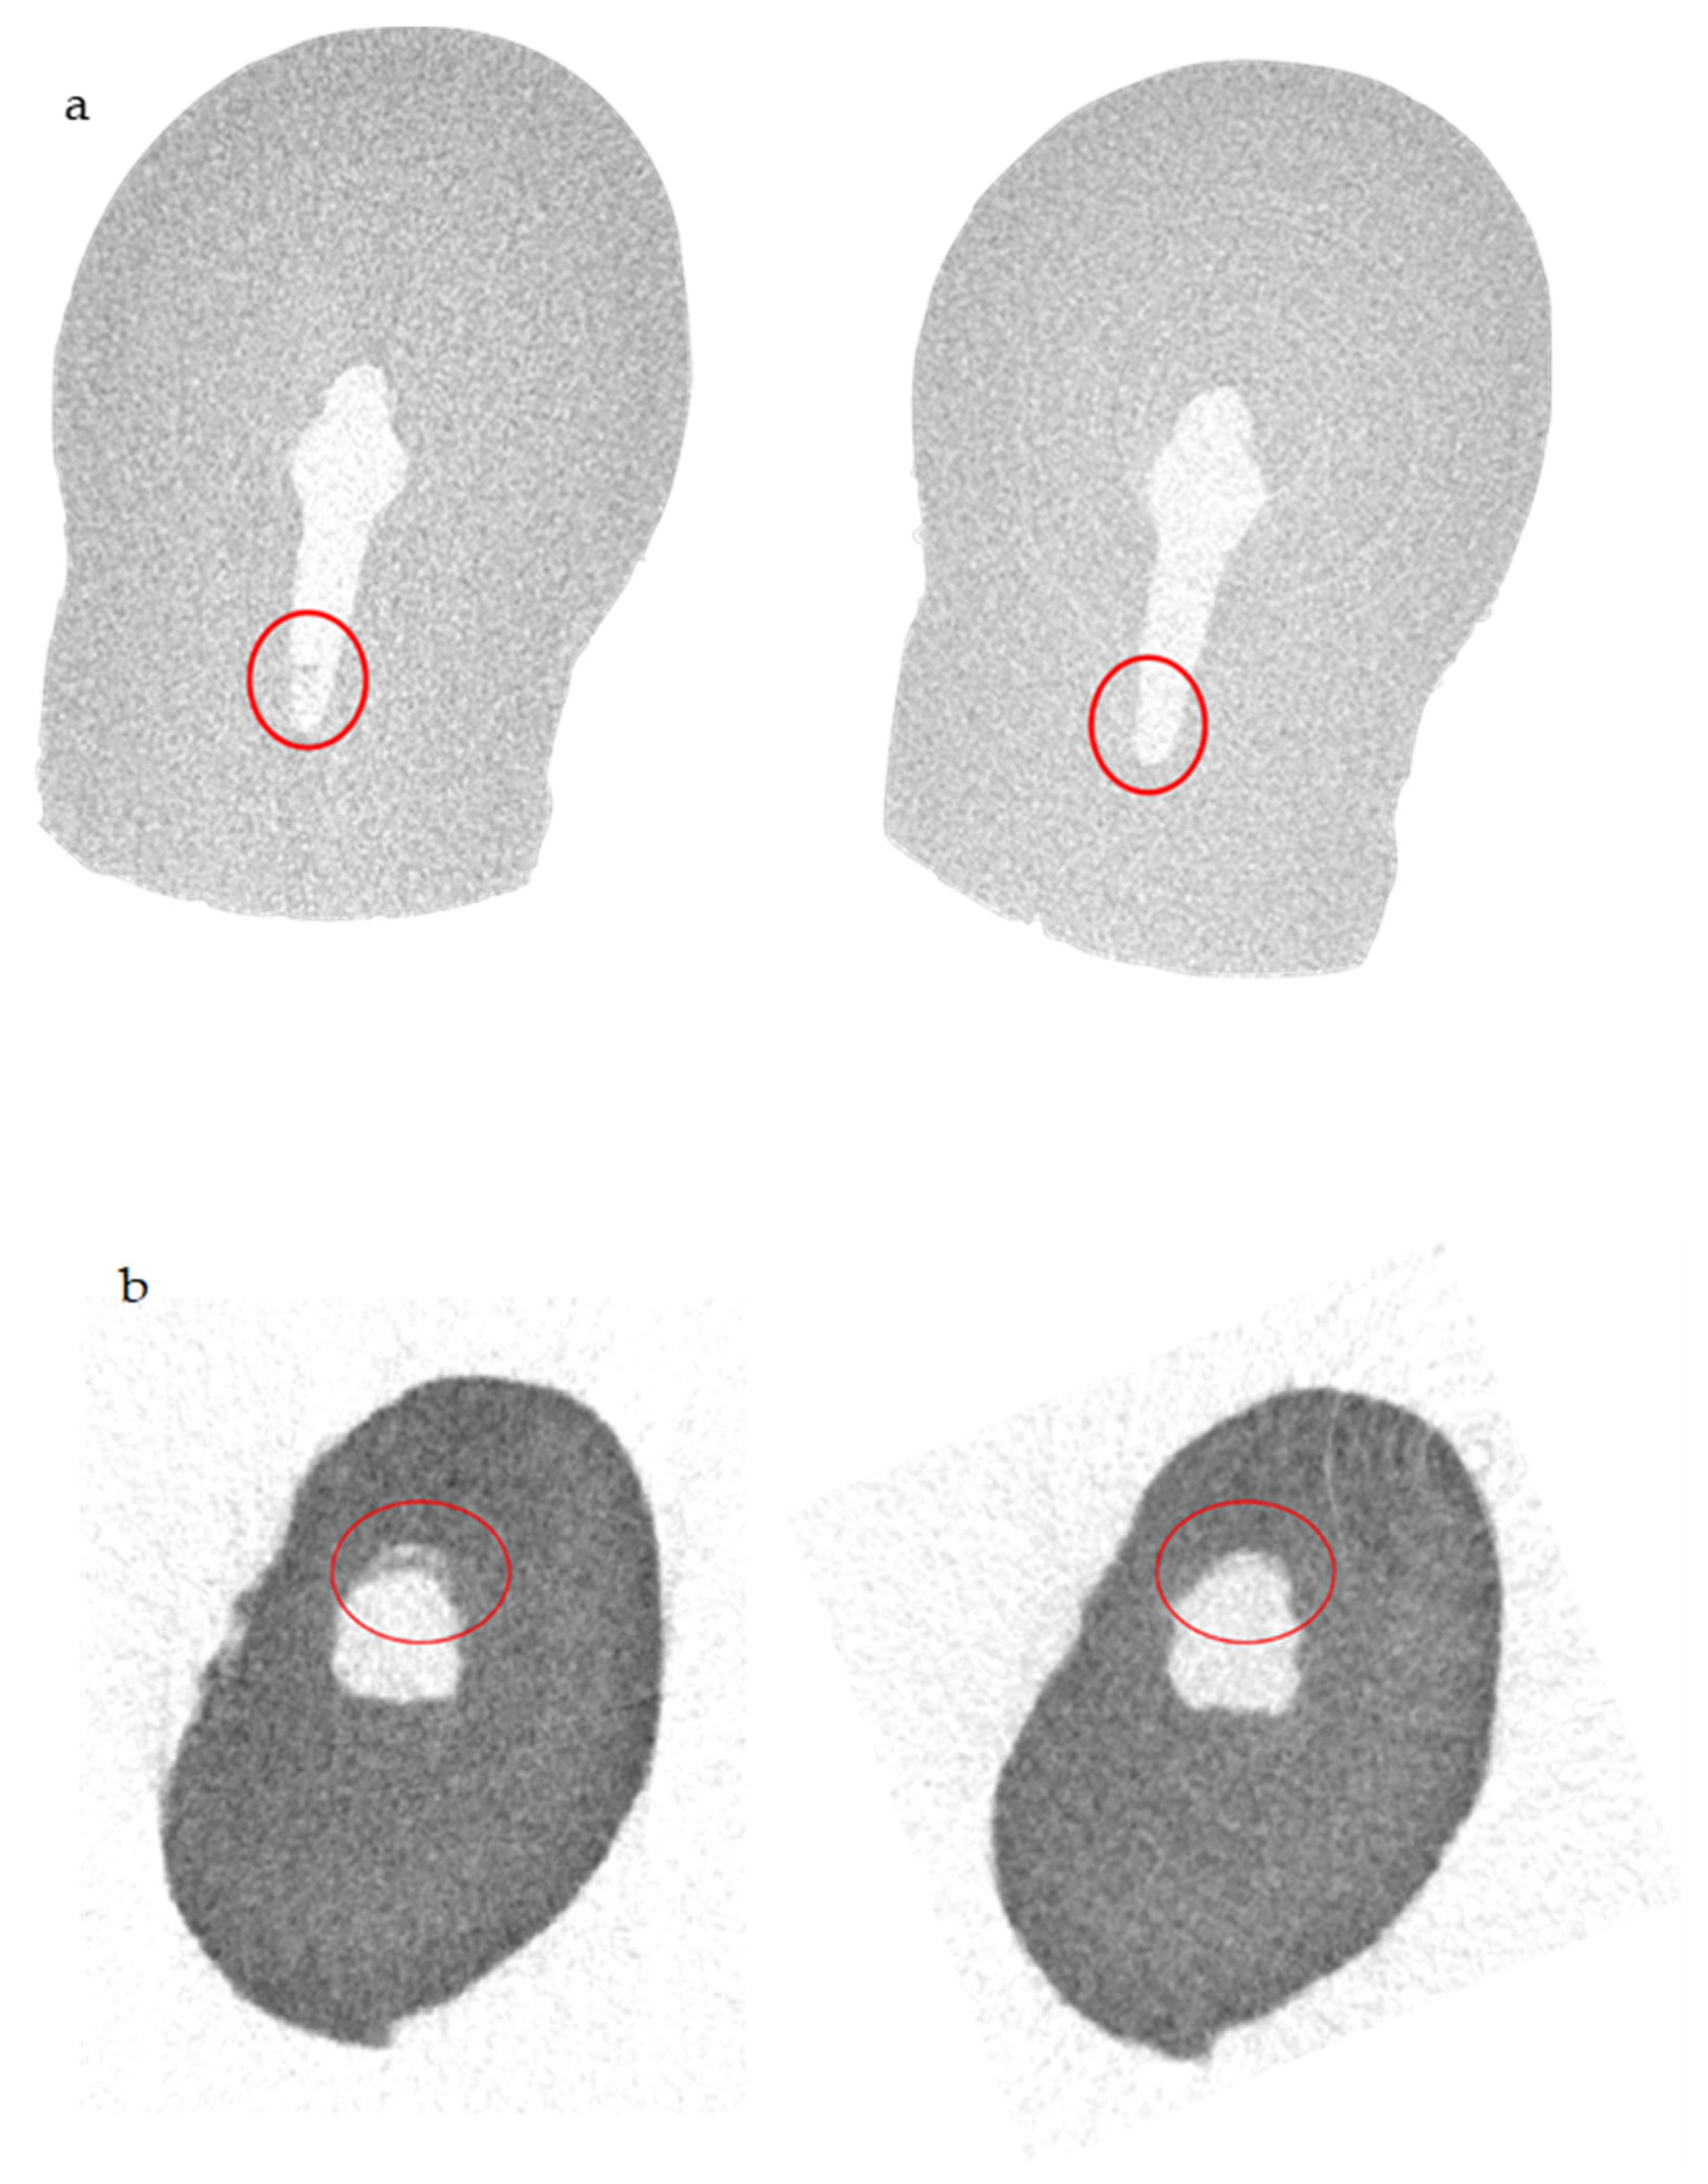

- Electric Current Activation Group (n = 5) (EB Group): The specimen was irrigated with 5 mL of NaOCl at 5.25% preheated using TruNatomy irrigation needle (Dentsply Sirona). For the electric current activation, ElectroBond (Patent No. WO03/002014 PCT/IB02/02565, Rome, Italy) was used. ElectroBond delivered a direct current (DC) between the endodontic dentin (working as cathode) and the irrigating solution (working as anode) [14]. The tested ElectroBond automatically induced an electric flow over 20 μA throughout the irrigating solution through the endodontic dentine during the application procedure. To permit electricity conduction under in vitro conditions, the tooth to be tested was surrounded by a transmitting medium inside the ProTrain (Figure 1).

| SkyScan 1072—ISS | Before Irrigant Activation | After Irrigant Activation |

|---|---|---|

| Volume of shaped root canal (mm3) | 8.0717 ± 0.0002 | 8.0717 ± 0.0002 |

| Volume of AHTD (mm3) | 0.3507 ± 0.0001 | 0.1506 ± 0.0008 |